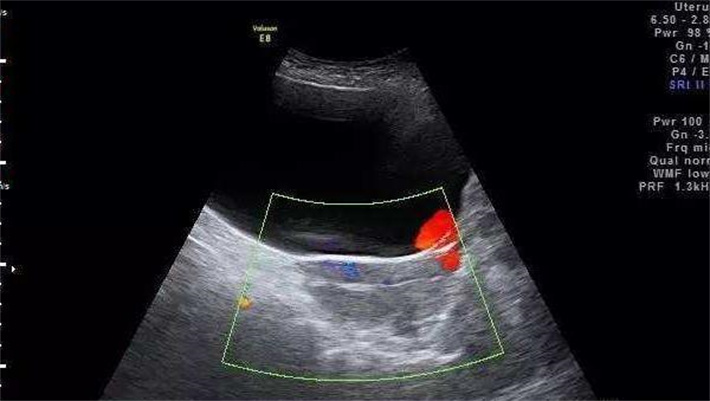

阴道B超监测:实时追踪卵泡大小、数量、分布情况,记录主导卵泡(直径≥14mm)与小卵泡比例,判断卵泡发育是否同步。

当主导卵泡直径达到18-20mm(成熟标准),且至少3枚卵泡直径≥16mm时,专家会安排注射“夜针”(人绒毛膜促性腺激素,HCG)。用药剂量会根据卵泡数量、激素水平进行个性化调整。

术中:取卵手术在无菌手术室开展,采用静脉麻醉(全程无痛,术后快速苏醒)。HRC专家会将装有穿刺针的超声探头置入阴道,通过实时超声影像定位卵泡位置,用细针(直径<1mm)经阴道穹窿穿刺进入卵泡,连接负压吸引装置,以负压抽吸方式将卵泡液(含卵子)吸出。